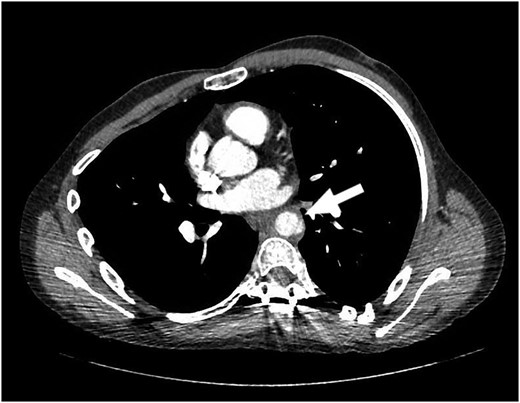

The patient returned to the hospital less than a week later in extremis. He had severe back pain and was diaphoretic. The patient was hypotensive and tachycardiac. He had no femoral pulses. Repeat CT scan revealed extension of the aortic injury in the abdominal aorta with no flow in the iliac (Figs 2–4). The patient was emergently taken to the operating room (OR) where the aorta, iliac and femoral vessels were unable to hold sutures. We were unable to repair this patient's aorta. Post-operatively, we spoke with the family, and the patient was allowed to expire.

Note contrast in the distal aorta but no contrast in the iliac arteries.